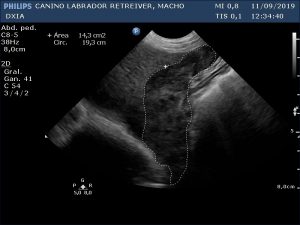

Ecografía Abdominal DXIA Scott

Lóbulo hepático.

Parénquima hepático homogéneo en lóbulos caudal a la vesícula biliar y lóbulo derecho próximo al estómago, pero en el resto del hígado se observa hepatomegalia (al presentar bordes hepáticos redondeados) junto con patrón marcado nodular que le da heterogenicidad. Se realiza PAF ecoguiada para su posterior análisis anatomopatológico, pero si no es suficiente la muestra se requerirá la realización de biopsia.

Primera Imagen Hígado DXIA Scott

Primera Imagen Hígado donde se obtuvo la PAF